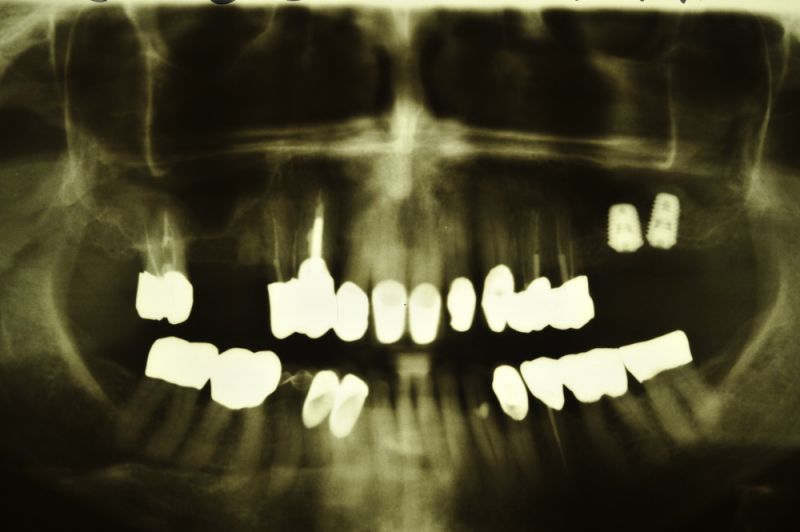

Genau das kann man dann auf dem Röntgenbild erkennen. So bildet sich innerhalb der Kieferhöhle, aber begrenzt durch die Kieferhöhlenmembran, neuer Knochen, der dann nachfolgend dem Implantat den knöchernen Halt gibt, den es unter späterer Belastung durch Kaudruck benötigt.

Wenn man so will, ermöglicht das Implantat, das wie ein Mittelmast das Zirkuszelt in die Höhe drückt, erst die Möglichkeit, dass der Hohlraum, der dann zwischen dem Zirkuszeltboden und der Mastspitze entsteht, sich nachfolgend mit Knochen auffüllt, so dass das Implantat am Ende des Einheilungsprozesses in voller Länge in neu gebildetem Knochen steht!

Alles in allem eine technisch sehr aufwändige Operation, verbunden mit erheblichem Materialeinsatz, aber am Ende der Schaffung neuen Knochens, in dem dann sehr gut und dauerhaft Implantate verankert werden können, um einen festsitzenden Zahnersatz zu installieren.